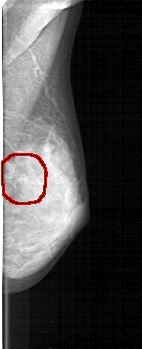

D_4130_1.LEFT_MLO

LEFT_MLO LINES 5221 PIXELS_PER_LINE 2116 BITS_PER_PIXEL 12 RESOLUTION 43.5 OVERLAY

FILE: D_4130_1.LEFT_MLO.OVERLAY

TOTAL_ABNORMALITIES 1

ABNORMALITY 1

LESION_TYPE CALCIFICATION TYPE FINE_LINEAR_BRANCHING DISTRIBUTION LINEAR

ASSESSMENT 3

SUBTLETY 3

PATHOLOGY MALIGNANT

TOTAL_OUTLINES 1

BOUNDARY